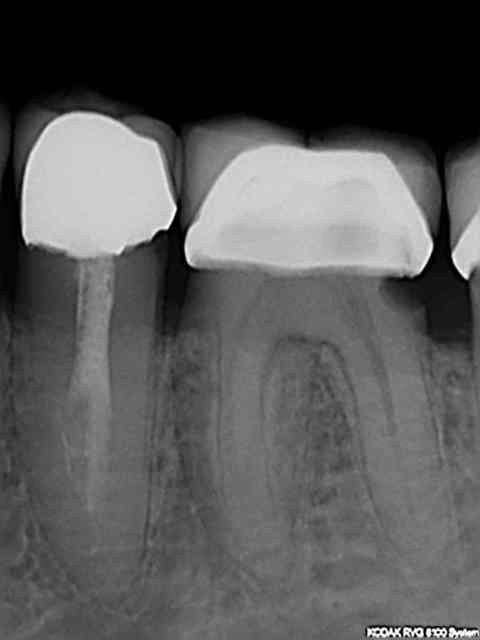

La nomenclature a aussi beaucoup changé en 30 ans a tel point que je suis complètement largué avec ces histoires de Z6 + Z3+ Z3 Je ne sais pas coter ces radios la radio de départ (dite de diagnostic) faisant partie d'un status pris un autre jour mais sur lequel j'avais coté la 47 et la 44 mais pas la 46.))))))